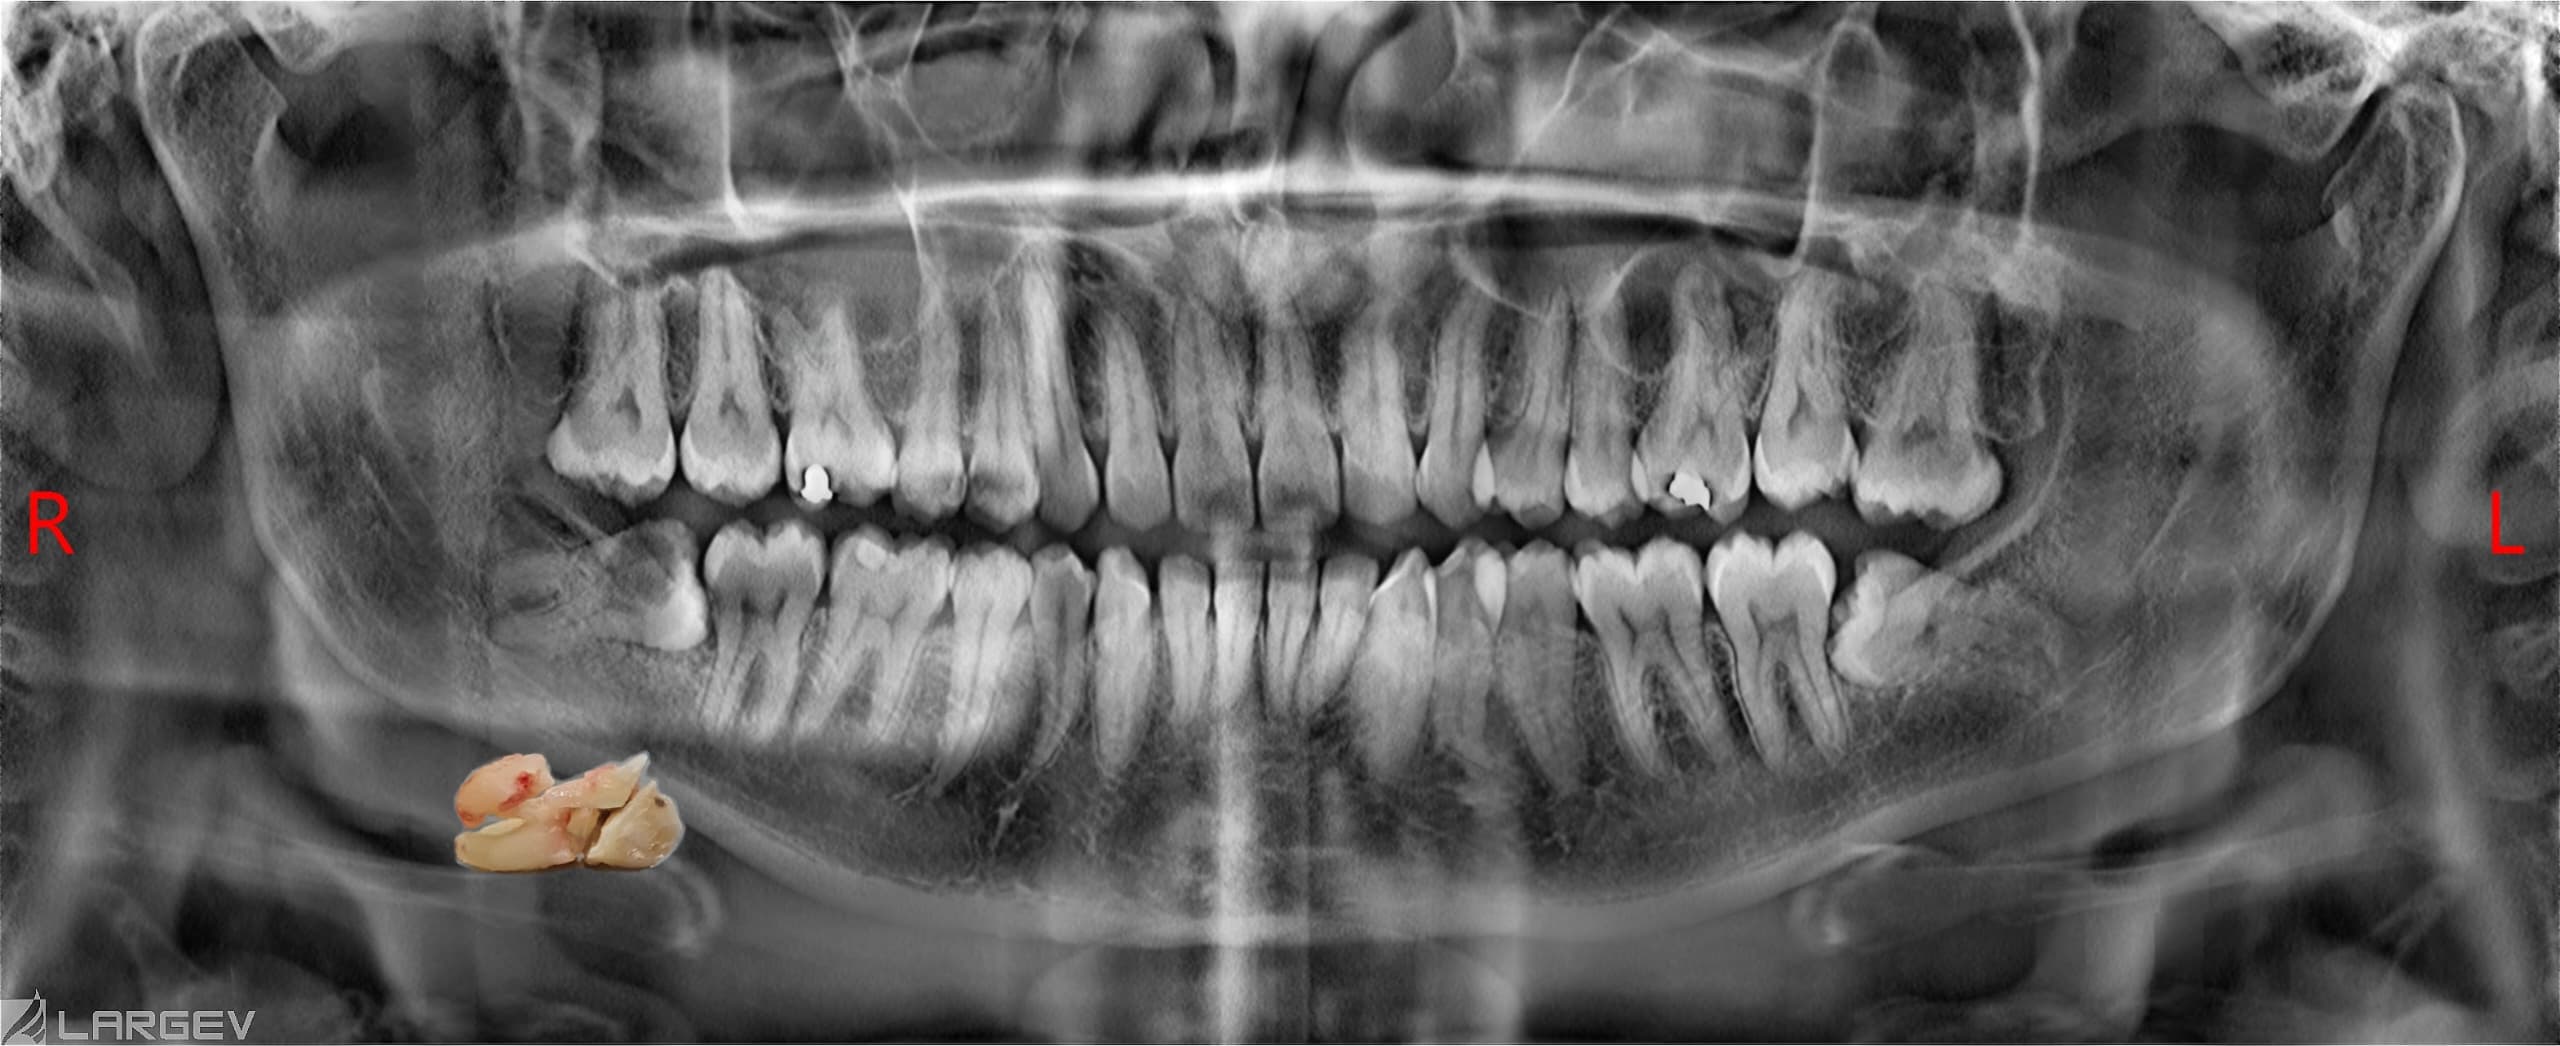

Before undergoing wisdom tooth surgery, a thorough evaluation and diagnosis are essential. X-rays and clinical examinations are conducted to determine the position of the wisdom teeth, their impact on surrounding teeth, and the best approach for extraction.